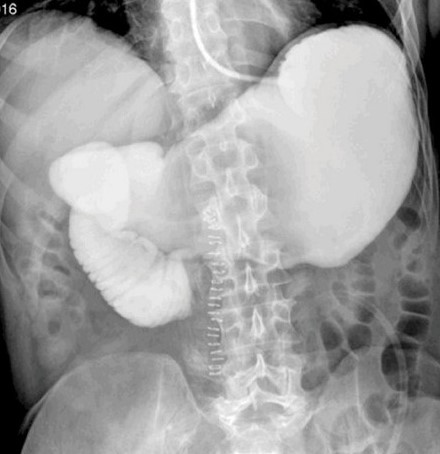

Abdominal computed tomography – Significant gastric and duodenal distension. Obstruction – severe narrowing at the third portion of the duodenum, anterior to the abdominal aorta and posterior to the superior mesenteric artery. Courtesy Dr. V. Penopoulos.